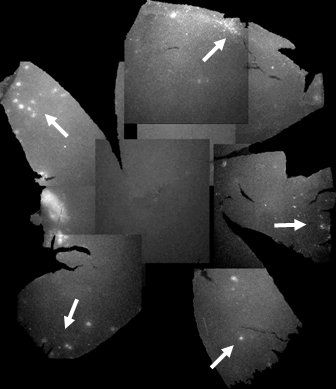

Figure 2. Composite flatmount images from a single TgN S334ter treated retina at P70. One rat eye from the group treated with intravitreal

glial-derived neurotrophic factor (GDNF)-secreting mouse embryonic stem (mES) cells at P21. Spots of increased hyperfluorescence

(white), indicative of colonies of green fluorescent protein (GFP)-expressing mES cells, are mainly seen in the peripheral

retina (arrows).